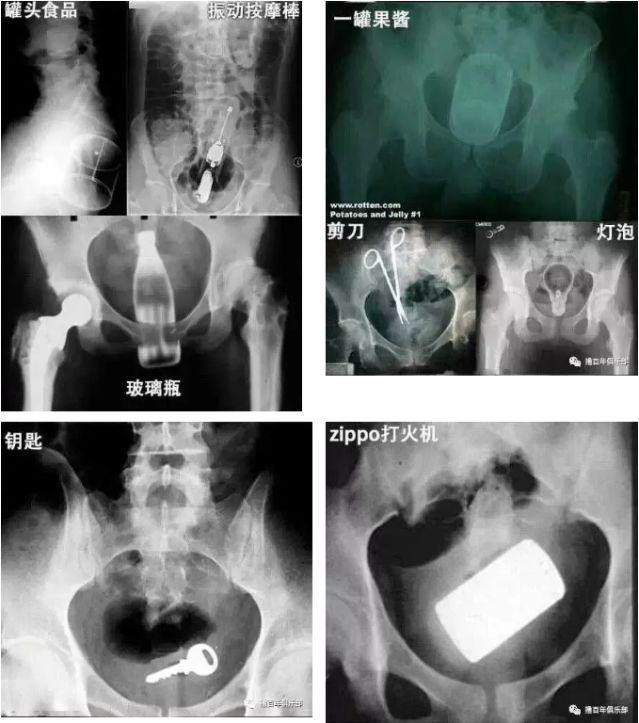

来一起看下图的x光照片吧,只有你想不到没有别人做不到的——

简而言之,就是直肠里出现除了粪便以外的其他东西,比如:从嘴巴里进入的坚硬的果核、鱼刺、鸡骨头;从肛门进入的灯泡、按摩棒、玻璃药瓶、陀螺、蜡烛、圆柱形金属瓶等。甚至还有常见的长条状的蔬菜或生命体,如黄瓜、火腿肠、茄子、苦瓜……直肠异物的种类可谓五花八门。